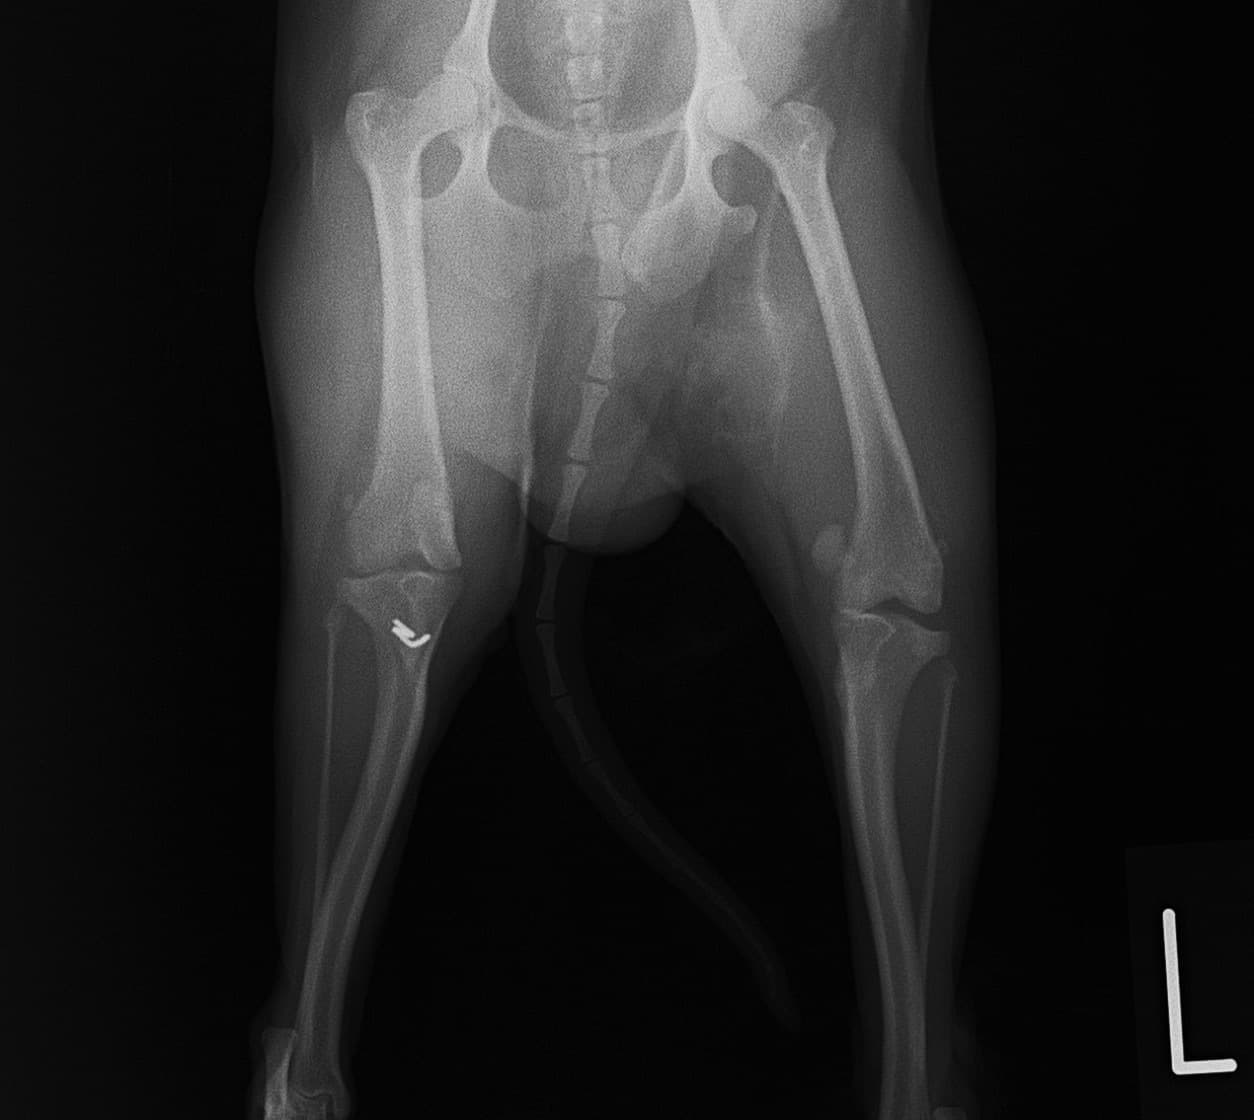

■ 症例22 ポメラニアン 1歳5か月 去勢雄

左後肢の挙上を主訴に来院した。整形学的検査、レントゲン検査より左右の膝蓋骨脱臼(左GradeⅡ〜Ⅲ、右Grade Ⅱ)を認めた。また、脛骨の前方引き出し試験の際に、引き出し兆候は認められないものの、疼痛が認められたため、前十字靭帯の損傷が疑われた。術中における、目視および関節内の操作によって、前十字靭帯の損傷や過伸展といった異常が認められなかったため、膝蓋骨脱臼の整復のみ実施した。手術手技は縫工筋及び内側広筋の解放、脛骨粗面の外側転位、滑車ブロック形造溝術、内外側関節包の縫縮を実施した。本症例は跛行もなく経過良好である。しかし、頸骨高平部の角度(TPA)が 右26.2°、左24.9°であり、解剖学的に前十字靭帯損傷のリスクが高いことから今後の経過に注意が必要である。